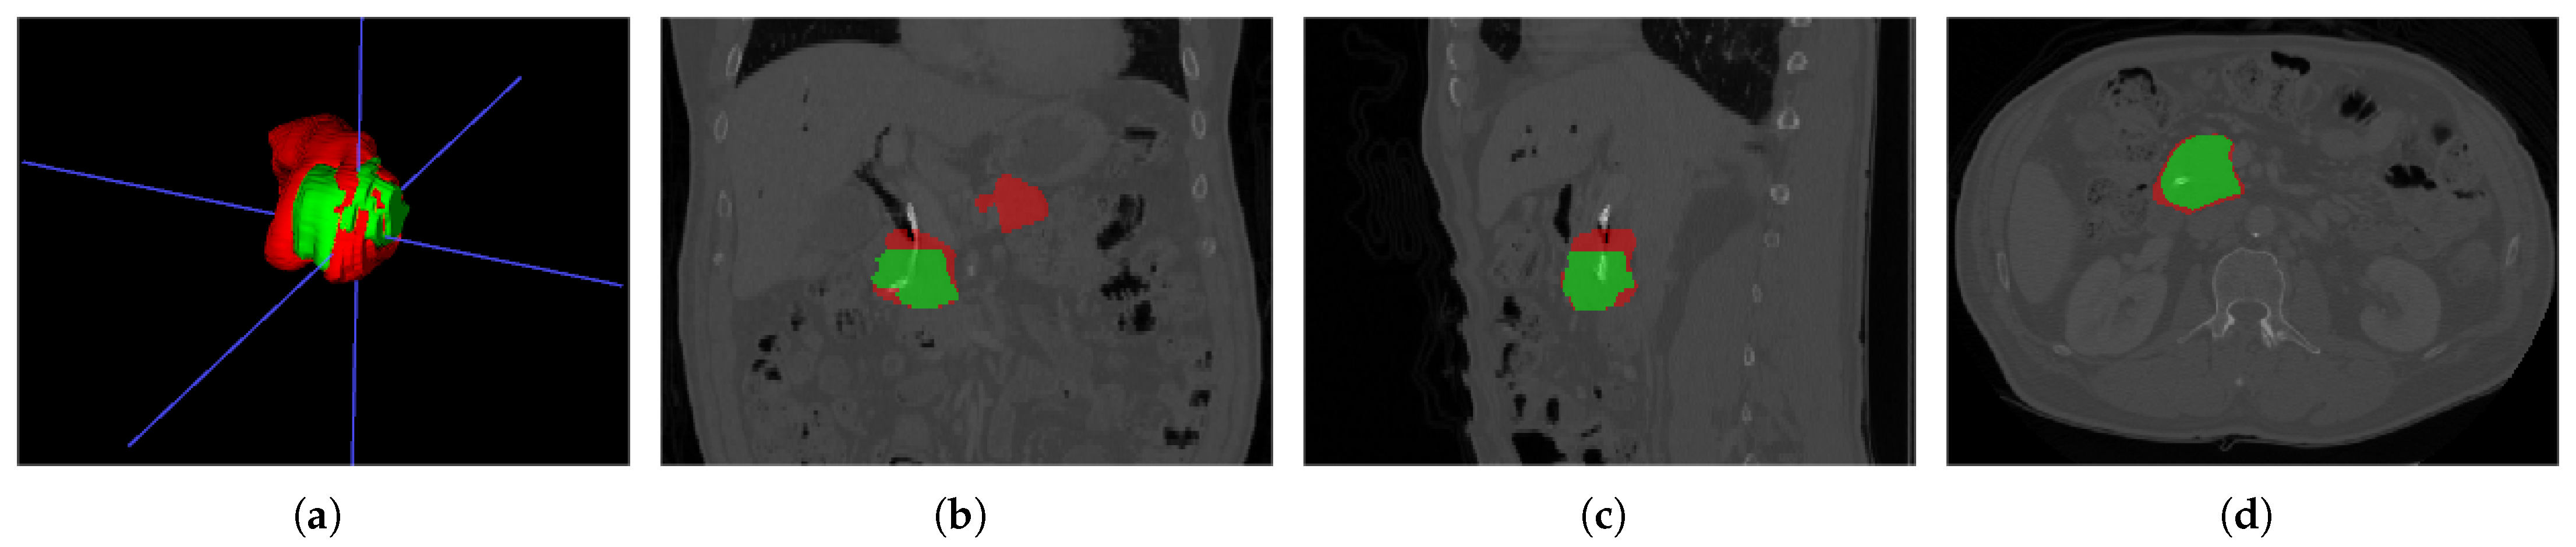

As shown in Figure 3, ITK-SNAP [] was used to visualize CT images, where the red labels represent healthy pancreatic tissues and the green parts represent PC tissues. The task of this dataset is to subdivide the pancreas and the PC, the latter being relatively challenging.

Figure 3.

MSD sample data pancreas_004.nii.gz: (a) 3D visualization of pancreas and PC, (b) main view, (c) left view, and (d) top view.